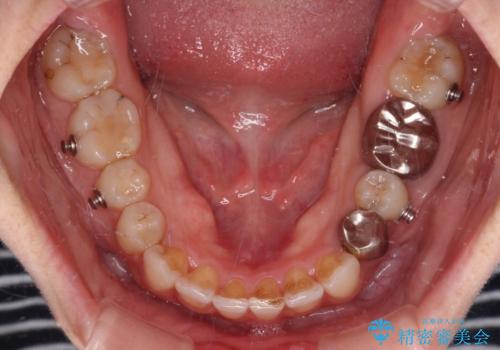

- インビザライン

- 前歯のデコボコと深い咬み込みを気にして来院された患者様です。

インビザラインを用いて、前歯の叢生を解消するとともに、深い咬み合わせ(ディープバイト)を改善していくこととしました。

奥歯を後方に直立させることで深い咬み合わせを改善を図り、隠れていた下顎前歯が見えるほどになりました。